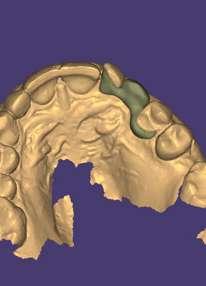

Fase 1: disyunción con MARPE

Tras colocar la anestesia palatina infiltrativa, el disyuntor osteo-soportado con tornillo hexagonal, se fijó de forma segura mediante los mini-tornillos utilizando un contra-ángulo de baja velocidad. Ese mismo día, se inició la expansión con pauta de 1 vuelta al día (0,16 mm por vuelta). Tras 43 días, se apreció la apertura de diastema inter-incisal y se continuó dando vueltas durante 18 días más hasta conseguir la corrección de la mordida cruzada posterior (Ilustración 5).

 Expansión confirmada mediante superposición de los modelos maxilares digitales previos y posteriores al tratamiento mediante MARPE (Ilustración 6). Se obtuvo un aumento transversal del 5,14 mm a nivel de los primeros molares.

Ilustración 6. Superposición del modelo inicial (azul) modelo y post-disyunción (gris).